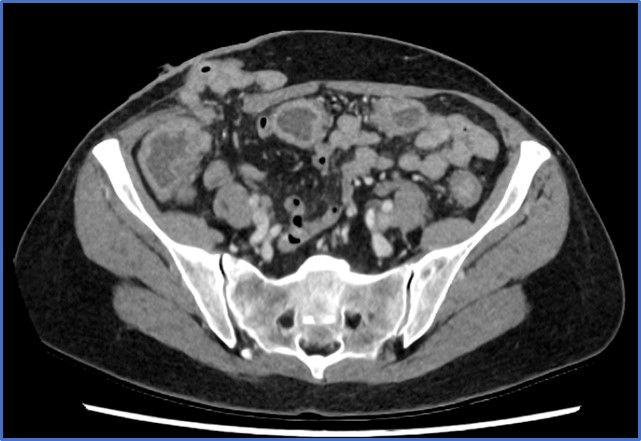

En pacientes con ICD grave puede estar indicado el uso de TC con contraste intravenoso para descartar complicaciones cómo megacolon tóxico (dilatación del colon de > 7cm) o perforación intestinal que pueden precisar una intervención quirúrgica urgente.

Los hallazgos más frecuentes incluyen engrosamiento mural del colon (puede verse como el signo del “doble halo” o “signo de la diana”, que consiste en 2 o 3 anillos concéntricos con diferentes valores de atenuación.) (ver imagen 1), cambios en la grasa pericólica y ascitis. El «signo del acordeón», es muy sugestivo de colitis pseudomembranosa. Para poder observar esta imagen del acordeón hay que administrar contraste por vía oral, que queda atrapado entre los pliegues haustrales edematizados (28). Es indicativo de edema severo en el colon por lo que también puede aparecer en enfermedad de Crohn o colitis isquémica.

Imagen 1: Imagen de TC de paciente con ileostomía que desarrolló infección por CD en la que se observa el “signo del halo” o “signo de la diana”.